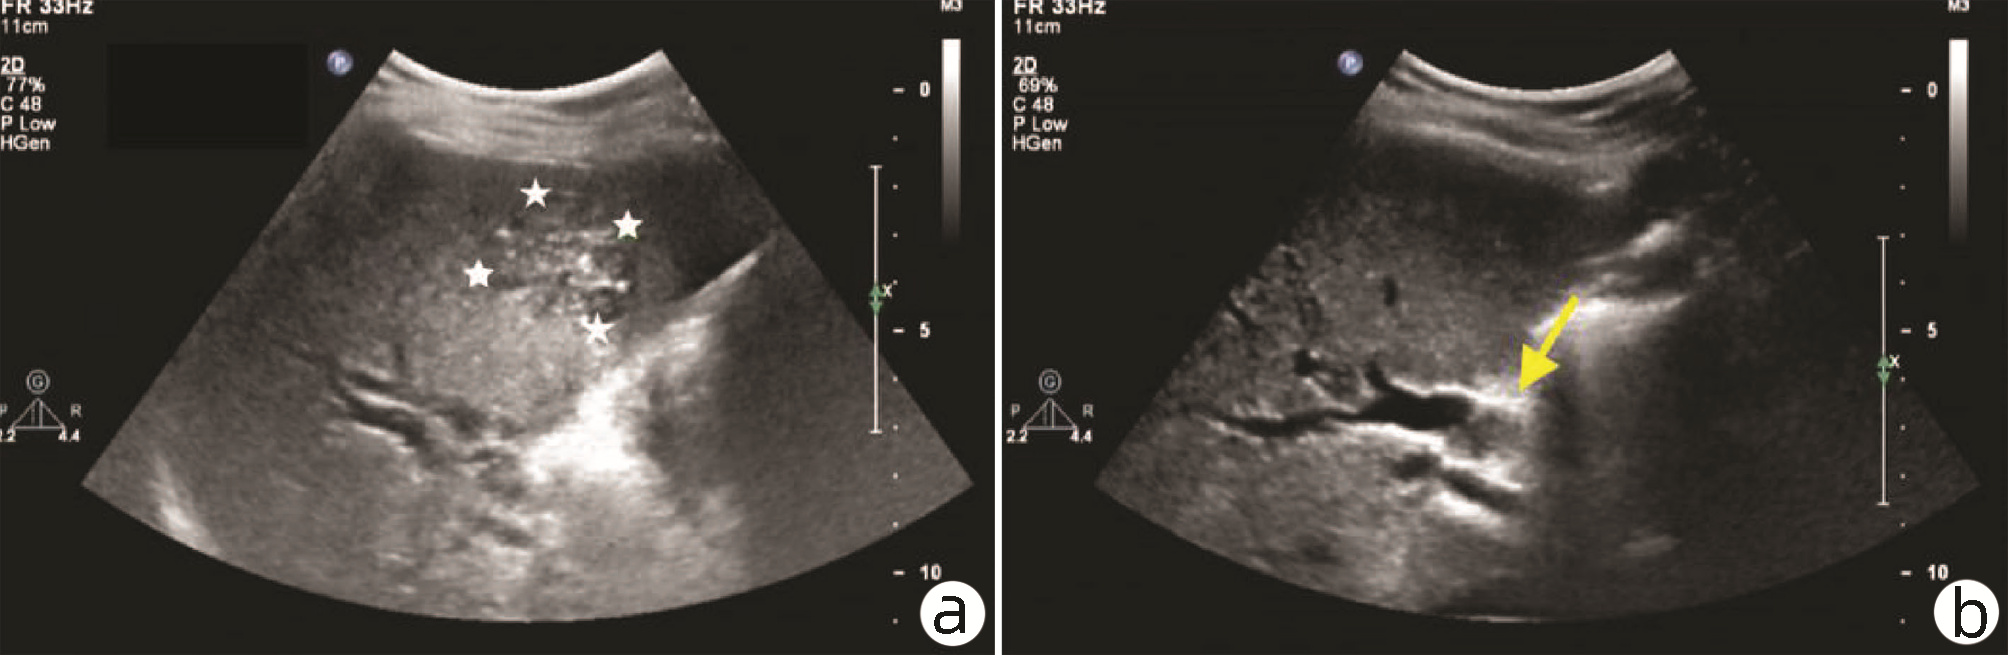

肝细胞癌合并胆管癌栓1例报告

2022, 38(8): 1872-1874. DOI: 10.3969/j.issn.1001-5256.2022.08.028

摘要(803) HTML (455) PDF (3665KB)(82)